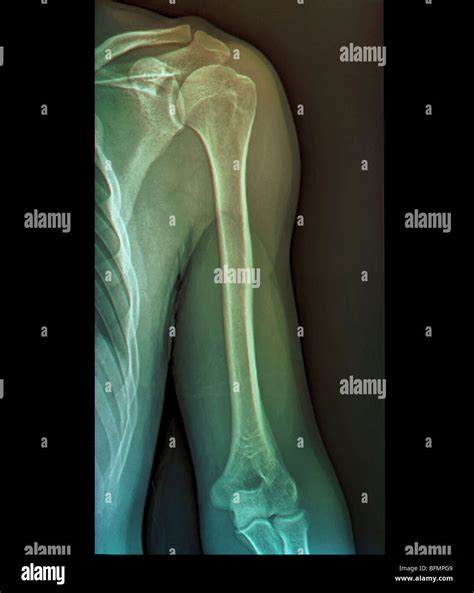

The shoulder joint is a ball-and-socket joint composed of three main bones: the humerus (upper arm bone), the scapula (shoulder blade), and the clavicle (collarbone). The joint is stabilized by a network of muscles, tendons, and ligaments, which allow for a wide range of motion. Understanding the anatomy is essential for interpreting X Ray Shoulder Joint images accurately.

• Fractures: Breaks in the bones of the shoulder, such as the humerus, scapula, or clavicle.

The X Ray Shoulder Joint procedure involves several steps to ensure accurate imaging:

1. The patient is positioned in front of the X-ray machine, usually standing or sitting.

2. The technician may ask the patient to move the arm into different positions to capture various angles of the shoulder joint.

3. Multiple images are taken to provide a comprehensive view of the shoulder, including the front, side, and top views.

4. The entire process typically takes about 15-20 minutes.

During the procedure, it is important for the patient to remain still to avoid blurring the images.